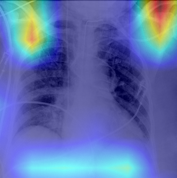

The areas of significant interest used by the CNN for discrimination purposes are identified using a qualitative analysis based on a Gradient-weighted Class Activation Mapping (Grad-CAM) [38]. This is an explainability method that serves to provide insights about the manners on how deep neural networks learn, pointing to the most significant areas of interest for decision-making purposes. The method uses the gradients of any target class to flow until the final convolutional layer, and to produce a coarse localization map which highlights the most important regions in the image identifying the class. The result of this method is a heat map like those presented in Fig. 1, in which the colour encodes the importance of each pixel in differentiating among classes.

The regions of interest identified by the network, were analyzed qualitatively using Grad-CAM activation maps [38]. Results shown by the activation maps, permit the identification of the most significant areas in the image, highlighting the zones of interest that the network is using to discriminate. In this regard, Fig. 1, presents examples of the Grad-CAM of a control, a pneumonia, and a COVID-19 patient, for each of the three experiments considered in the paper. It is important to note that the activation maps are providing overall information about the behaviour of the network, pointing to the most significant areas of interest, but the whole image is supposed to be contributing to the classification process to a certain extent.

The second row in Fig. 1 shows several prototipical results applying the Grad-CAM techniques to experiment 1. The examples show the areas of significant interest for a control, pneumonia and COVID-19 patient. The results suggest that the detection of pneumonia or COVID-19 is often carried out based on information that is outside the expected area of interest, i.e. the lung area. In the examples provided, the network focuses on the corners of the XR image or in areas around the diaphragm. In part, this is likely due to the metadata which is frequently stamped on the corners of the XR images. The Grad-CAM plots corresponding to the experiment 2 (third row of Fig 1), indicates that the model still points towards areas which are different to the lungs, but to a lesser extent. Finally, the Grad-CAM of experiment 3 (fourth row of Fig 1) presents the areas of interest where the segmentation procedure is carried out. In this case, the network is forced to look at the lungs, and therefore this scenario is supposed to be more realistic and more prone to generalizing as artifacts that might bias the results are somehow discarded.

We stand on the fact that automatic diagnosis is much more than a classification exercise, meaning that many factors have to be had in mind to bring these techniques to the clinical practice. To this respect, there is a classic assumption in the literature that the associated heat maps –calculated with techniques such as Grad-CAM– provide a clinical interpretation of the results, which is unclear in practice. In light of the results shown in the heat maps depicted in Fig. 1, we show that experiment 1 must be carefully interpreted. Despite the high-performance metrics obtained in experiment 1, the significant areas identified by the network are pointing towards certain areas with no clear interest for the diagnosis, such as corners of the images, the sternum, clavicles, etc. From a clinical point of view, this is clearly biasing the results. It means that other approaches are necessary to force the network to focus on the lungs area. To this respect, we have developed and compared the results with two preprocessing approaches based on cropping the images and segmenting the lungs area (experiment 2 and experiment 3). Again, given the heat maps corresponding to experiment 2, we also see similar explainability problems to those enumerated for experiment 1. Reducing the area of interest to that proposed in experiment 2 significantly decreases the performance of the system due to the removal of the metadata that usually appear in the top left and/or right corner, and to the removal of areas which are of interest to categorize the images but have no interest from the diagnosis point of view. However, while comparing experiment 2 and 3, performance results improve in the third approach, which focuses on the same region of interest but with a mask that forces the network to see only the lungs. Thus, results obtained in experiments 2 and 3 suggest that eliminating the needless features extracted from the background or non-related regions improves the results. Besides, the third approach (experiment 3), provides more explainable and interpretative results, with the network focusing its attention only in the area of interest for the disease. The gain in explainability of the last method is still at the cost of a lower accuracy with respect to experiment 1, but the improvement in explainability and interpretability are considered critical to translate these techniques to the clinical setting. Despite the decrease in performance, the proposed method in experiment 3 has provided promising results, with an Acc of , BAcc of , GMR of and AUC of .

The COVID-Net has also demonstrated being a good starting point for the characterization of the disease. Indeed, the outcomes of the paper suggest the possibility to automatically identifying the lung lesions associated with a COVID-19 infection (see Fig.1) by analyzing the Grad-CAM mappings of experiment 3, providing an explainable justification about the way the network works. However, the interpretation of the heat maps obtained for the control class must be carried out carefully. Whereas the areas of significant interest for pneumonia and COVID-19 classes are supposed to point to potential lesions (i.e. with higher density and/or with different textures in contrast to controls), the areas of significant interest for the classification in the control group are supposed to correspond to a sort of complement, potentially highlighting less dense areas. Thus, not meaning the presence of any kind of lesion in the lungs.